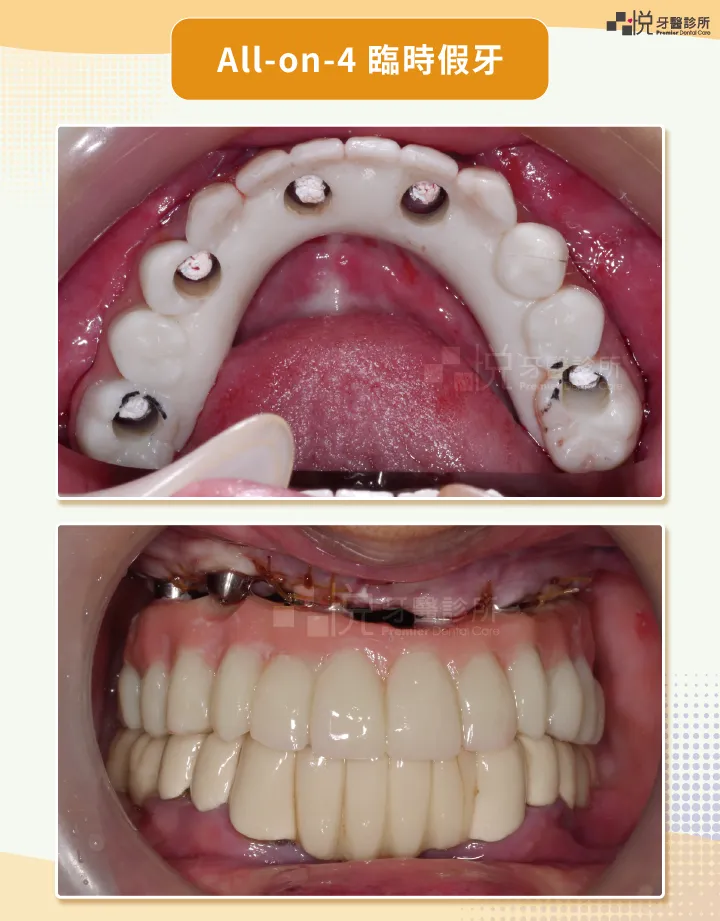

通常分成即刻負載( Immediate Implant Loading )和延遲負載 ( Delayed Implant Loading )。

「即刻負載」可立刻裝臨時假牙,「延遲負載」需等 3 到 6 個月後才能裝假牙。

植牙手術當天,植入人工牙根後,立即裝臨時假牙。

不會醜醜,沒有空窗期。